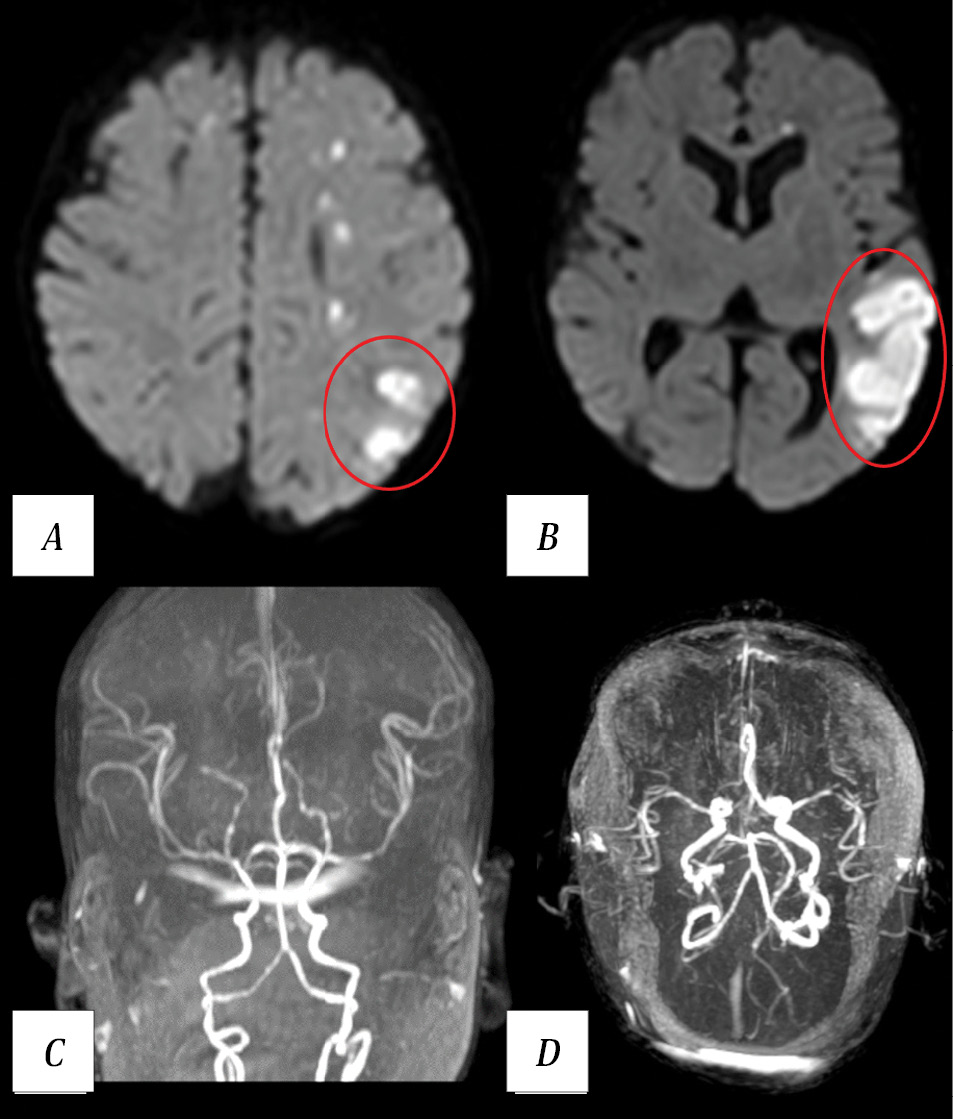

On day 2 postoperatively, focal motor epileptic seizures developed, manifesting as clonic jerking of the upper extremities (D < S), which were managed with midazolam infusion at 0.2 mg/kg/h and intravenous levetiracetam at 25 mg/kg/day. Emergency MRI revealed a watershed infarction zone in the left cerebral hemisphere (Fig. 8).

Fig. 8. Results of patient V. MRI on day 2 postoperatively.

A, B — brain MRI. Right DWI, axial plane. Watershed infarction zone in the left cerebral hemisphere (red ovals), multiple small ischemic foci. C, D — MR angiography, 3D reconstruction. Intracranial arterial blood flow remains intact.